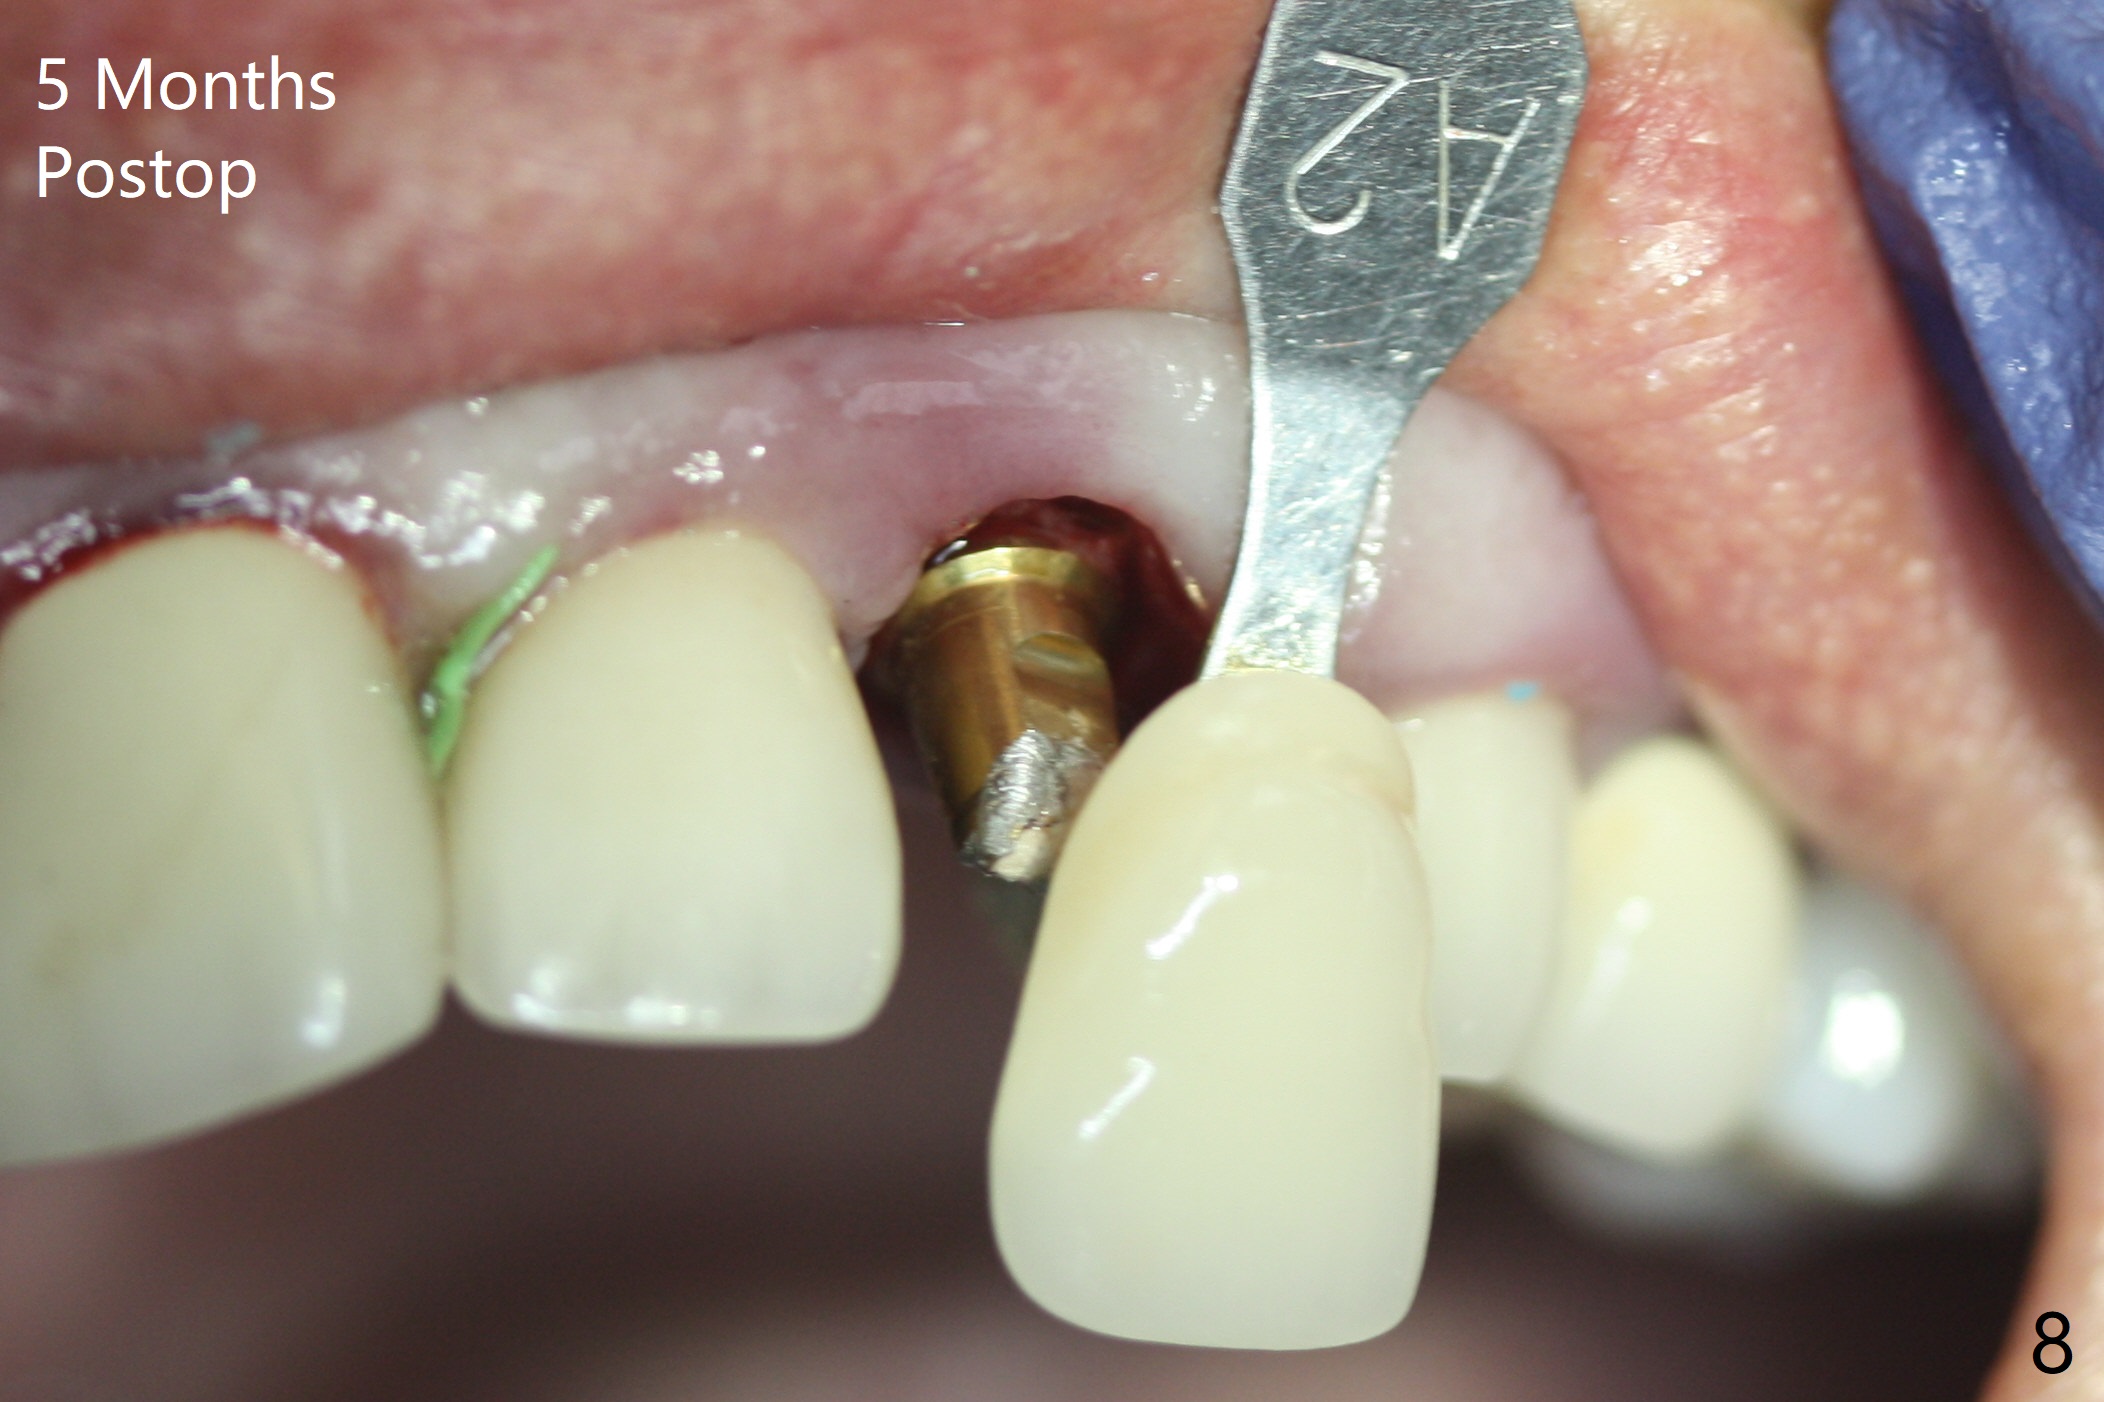

In spite of severe apical infection (Fig1,2 *), a thin narrow strip of the buccal plate (arrowheads, corresponding to the keratinized gingiva) is present when the tooth #11 is extracted. The thin bone keeps the bulging alveolus, i.e., reservoir for bone graft (Vanilla/Osteogen Fig.4 *) after placement of a 3.8x16 mm implant (Fig.3,4). A 4.5x1 mm temporary abutment, placed and trimmed for an immediate provisional, seems to be short in cuff. When an implant is placed deep to prevent periimplantitis, the cuff should be longer, i.e., 3 mm. X-ray should be taken for the depth confirmation after temporary abutment placement. Eight days postop, the mesial gingiva erythema has subsided (Fig.5 < (P: provisional)), while the apical swelling is no longer tender and most likely due to packed bone graft (*). Panoramic X-ray taken 2 weeks postop shows the clearance from the nasal cavity or the maxillary sinus (Fig.6). While the hard tissue around the implant seems to be healthy 5 months postop (Fig.7), the soft tissue is not (Fig.8). The temporary abutment is changed to a cemented one (4.5x5(2) mm) for impression (Fig.8). Since the neighboring crowns are PFM (Fig.6), the new crown will be made of the same material for shade match. Indeed PFM helps shade match in this case as well (Fig.9,10). Switching abutments (from temporary to cemented) makes it difficult to seat the crown. Post cementation X-ray leaves record for future contact loosening. The buccal gingiva remains erythematous associated with open margin (Fig.11 >) 1 year 4 months post cementation. There is no obvious bone loss 1 year 4 months post cementation (Fig.12). It appears that the crown and abutment need to be changed. Although the gingival margin remains erythematous, the gingival hemorrhage is basically lacking due to better oral hygiene during Shelter at Home (1 year 9 months post cementation, Fig.13). Change in abutment and crown will be conducted post coronavirus pandemic. In fact the abutment is incompletely seated (Fig.14 <). In addition, the tooth #12 is symptomatic with PARL associated with the buccal root (*). CBCT indicates possible buccal root fracture (Fig.15,16 ^) and loss of the buccal plate (Fig.16 <).